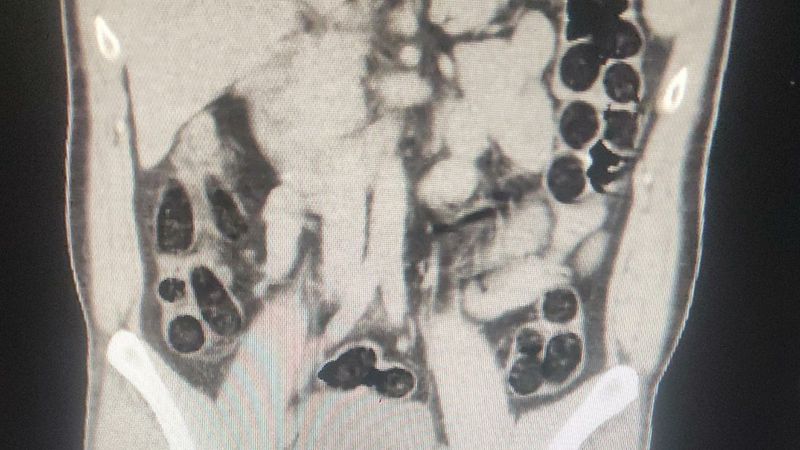

Hastanede çekilen röntgenlerinde birinin midesinde uyuşturucu tespit edildi. Şüphelinin, 76 paket halinde 714 gram eroini doğal yollarla çıkarılması sağlandı.